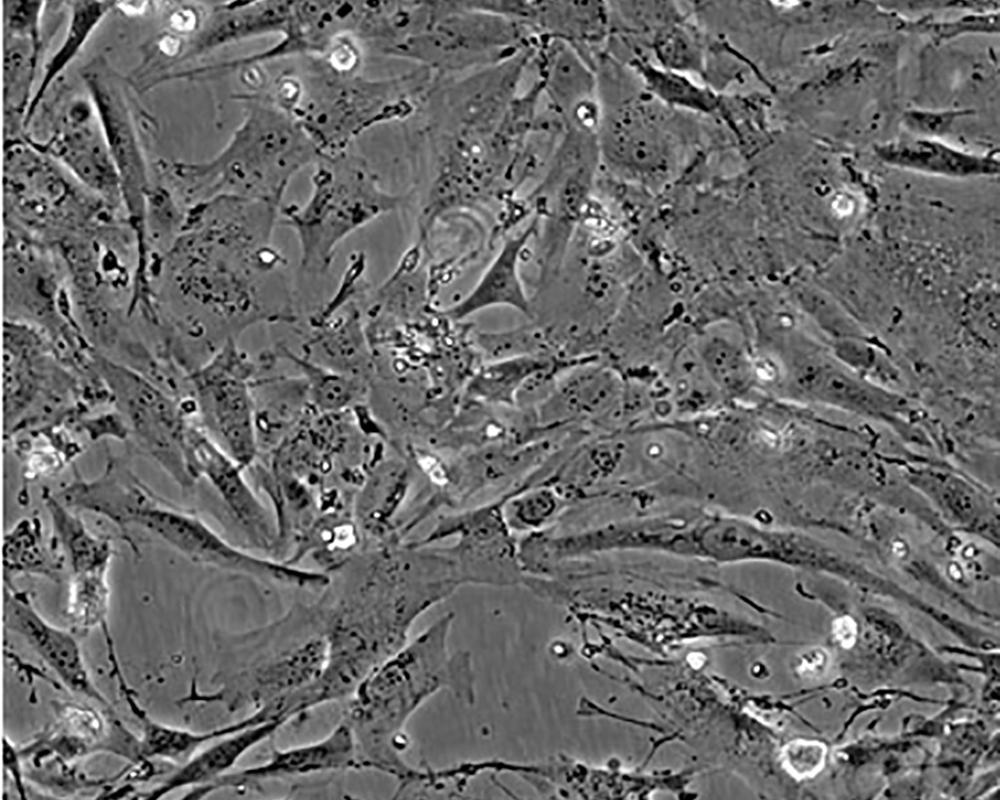

Hs 578T

產品名稱 Hs 578T

中文名稱 人乳腺癌細胞

組織來源 浸潤性導管癌;女性

形態特征 epithelial

細胞描述 The Hs 578T line had a mixed polygonal morphology initially, but a stellate cell type was selected for during passage and by cloning. Aggregates of casein protein granules, desmosomes, tight junctions, lipid droplets and vesicularized smooth endoplasmic reticulum were observed by electron microscopy. As with Hs 578Bst, no estrogen receptors or endogenous viruses were detected.

細胞傳代步驟 如果細胞密度達80%-90%,即可進行傳代培養。1. 棄去培養上清,用不含鈣、鎂離子的PBS潤洗細胞1-2次。2. 加2ml消化液(0.25%Trypsin-0.53mM EDTA)于培養瓶中,置于37℃培養箱中消化1-2分鐘,然后在顯微鏡下觀察細胞消化情況,若細胞大部分變圓并脫落,迅速拿回操作臺,輕敲幾下培養瓶后加少量培養基終止消化。3. 按6-8ml/瓶補加培養基,輕輕打勻后吸出,在1000RPM條件下離心4分鐘,棄去上清液,補加1-2mL培養液后吹勻。4. 將細胞懸液按1:2到1:5的比例分到新的含8ml培養基的新皿中或者瓶中